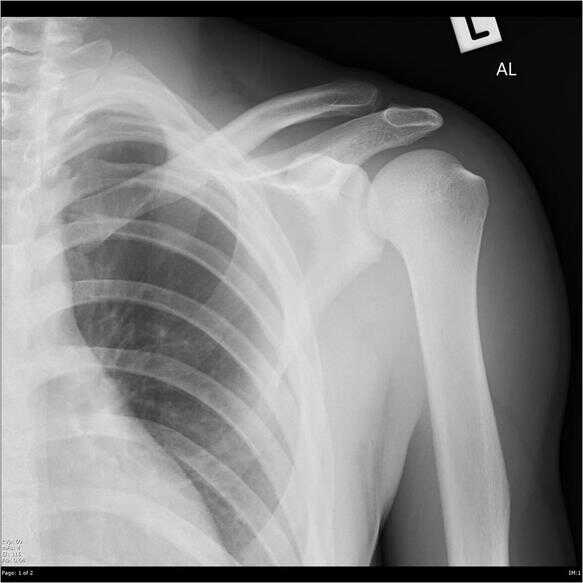

La luxación de la articulación acromioclavicular (también conocida como hombro separado) se produce cuando las dos superficies articulares de la articulación se separan. Se asocia a daños en los tejidos blandos de la articulación.

Suele producirse por un golpe directo en la articulación, o por una caída sobre una mano extendida.

La lesión es más grave si se produce la rotura del ligamento (acromioclavicular o coracoclavicular). Si se rompe el ligamento coracoclavicular, el peso del miembro superior no se sostiene y el hombro se desplaza hacia abajo. Esto aumenta la prominencia de la clavícula.

El tratamiento de la luxación de la articulación acromioclavicular depende de la gravedad de la lesión y del impacto en la calidad de vida. Las opciones de tratamiento van desde el hielo y el reposo hasta la cirugía de reconstrucción de los ligamentos.

Nota: esta lesión no debe confundirse con la dislocación de hombro, una lesión que afecta a la articulación glenohumeral.